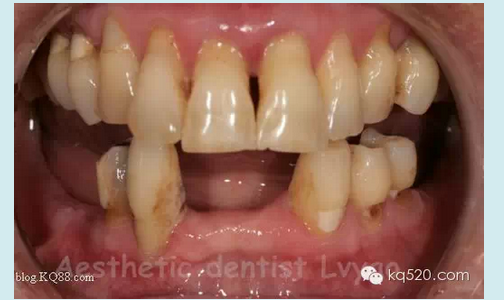

修復(fù)前口內(nèi)影像